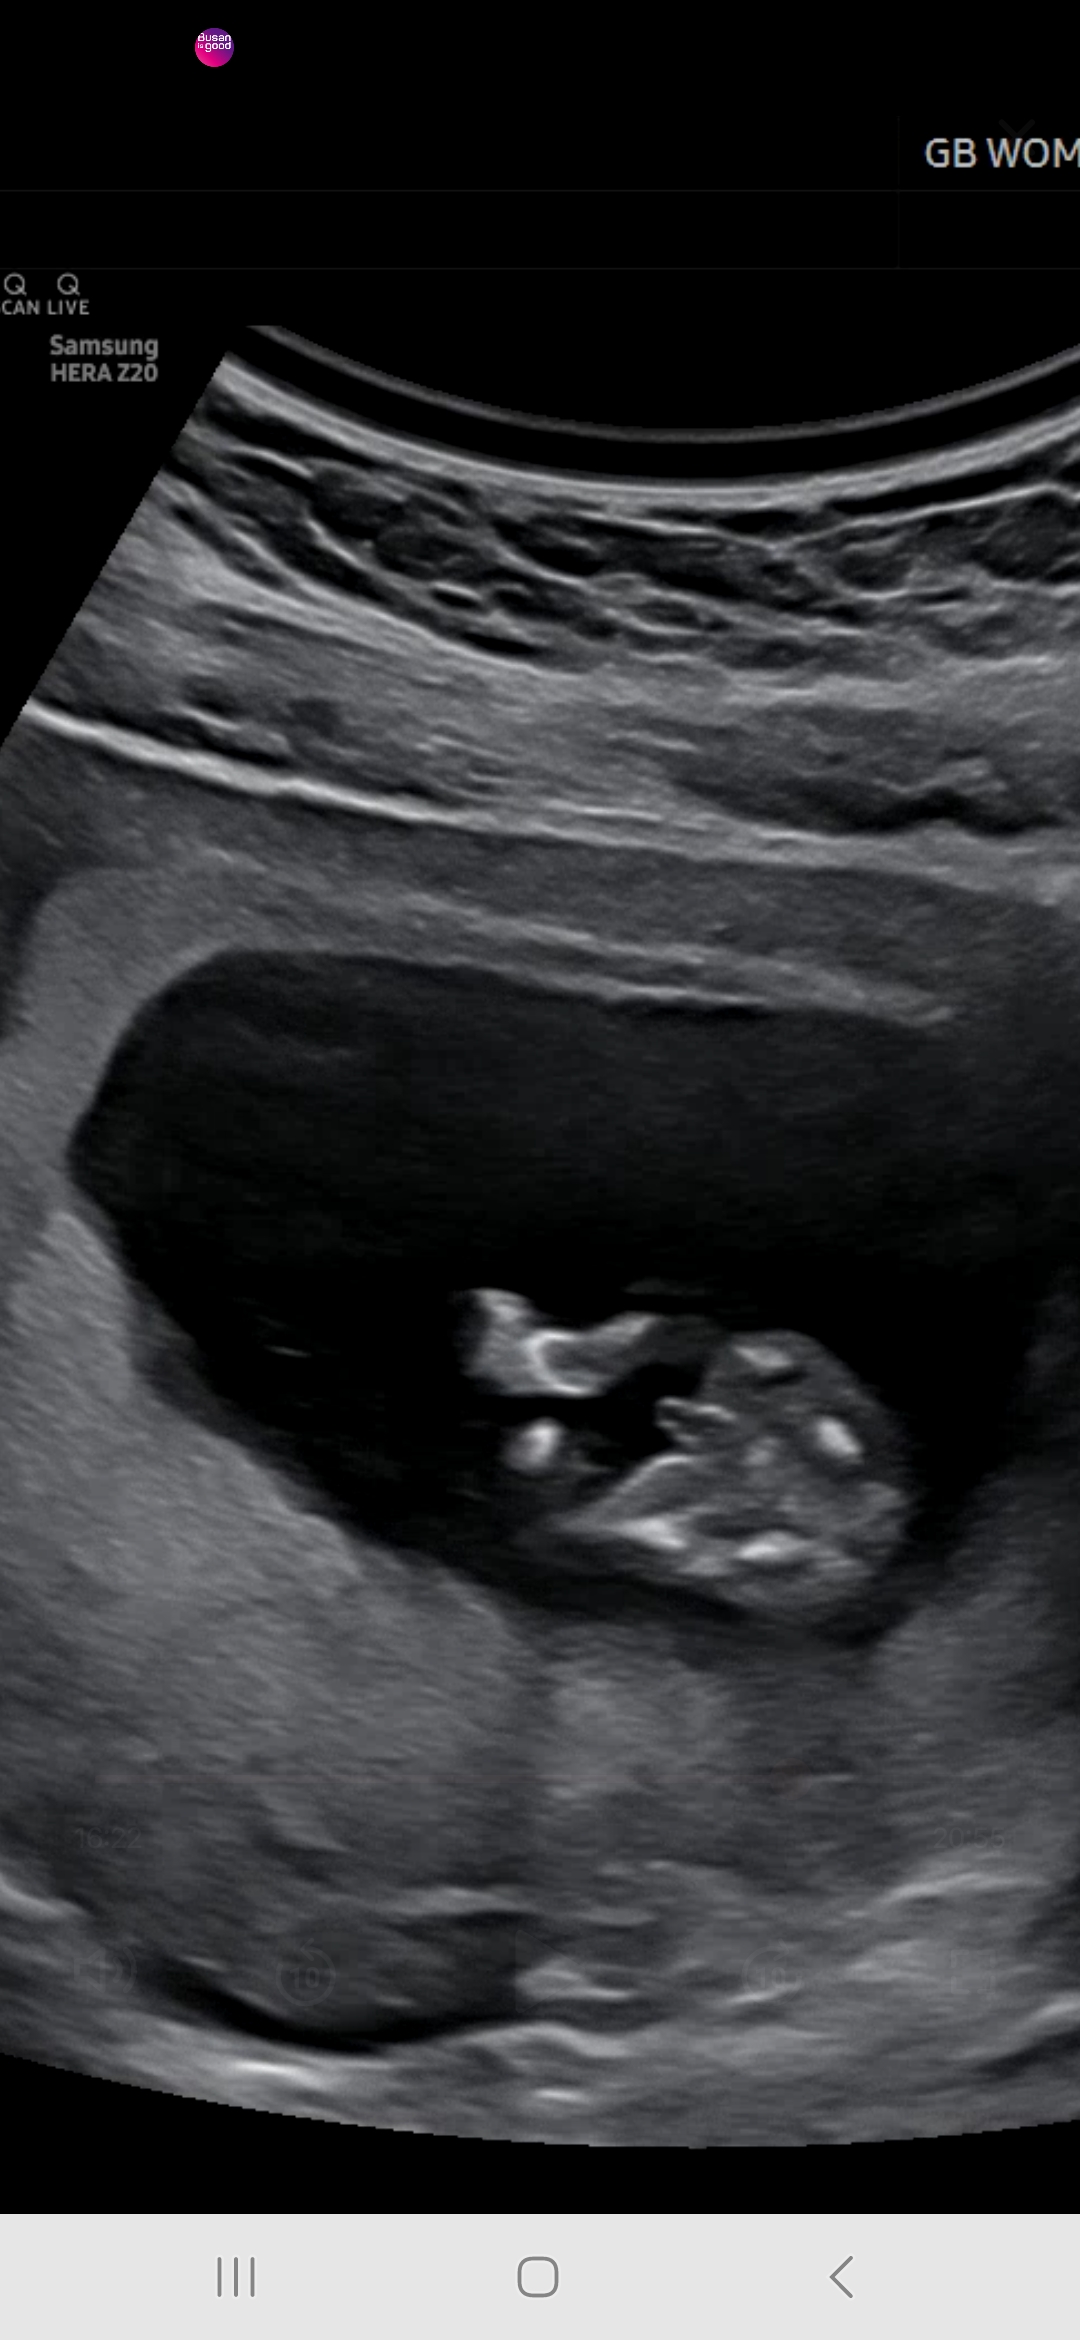

밑에서 찍은사진 성별

옆모습은 못보고 밑에찍은 사진으로 봣을땐 아들같은데 맞을까요? 12주1일에 찍은거에요

보통 저정도면 확정이라고는 하시던데 16주까지는 반전이 많아서 16주는 돼야 확정 가능하대요.